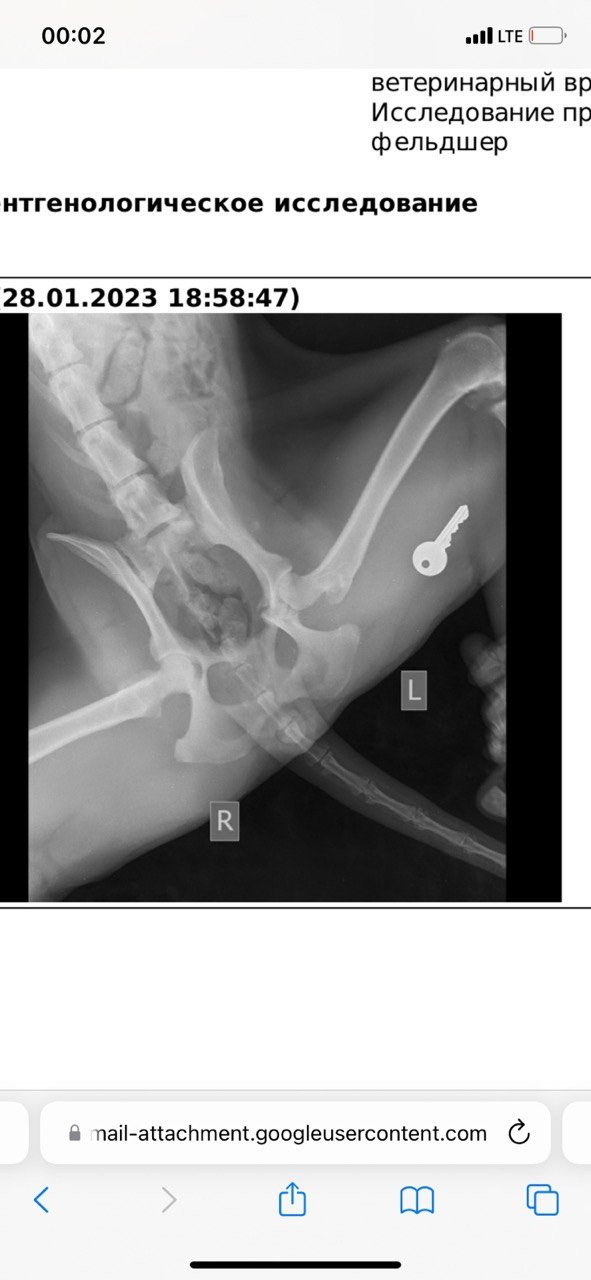

Это было утром примерно в 7:50 утра, я повез в ближайшую клинику (кое-как дотащил её до машины на руках, она весит 35 кг примерно, а у меня еще вторая собака была со мной, хорошо какая-то женщина увидела, помогла вторую довести до машины), но клиника оказалось закрытой, повёз в другое место. Там сделали снимки, оказалось, что удар пришелся в заднюю часть (как позже выяснилось - это был перелом вертлужной впадины).

Снимки в декабре и в феврале.

Середина декабря, потихоньку ходит уже самостоятельно.